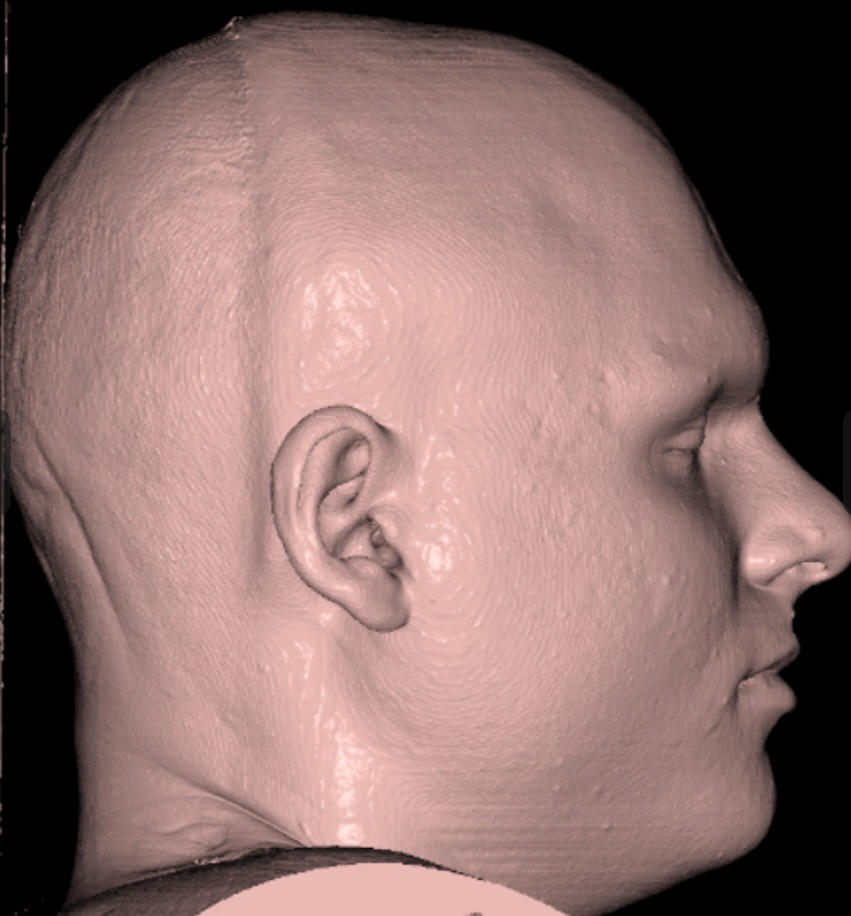

Here is how my side profile looks IRL:

Here is how my side profile looks IRL: